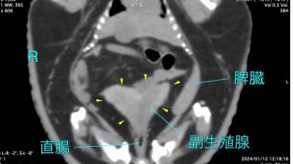

理論的に精嚢腺は超音波検査で明確になると思われますが、内臓領域とも重なることから、CT検査が最も診断に有用です。精嚢腺の拡大や軟化・硬結などが認められ、炎症などが潜在していると診断されます。